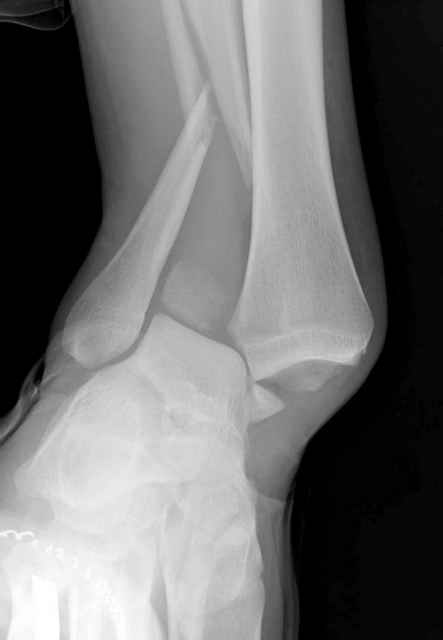

>На сделанных у нас снимках видно, что не все благополучно...

Неравномерность суставной щели может быть связана с разрывом глубокой порции дельтовидной связки и ротацией м/берцовой кости за счет поврежденных структур синдесмоза(репозиция ее на уровне перелома как-будто удовлетворительная).

Импрессия медиальной части суставной поверхности бывает при супинационном механизме перелома лодыжек (тип А по классификации АО). Здесь механизм пронациия+наружная ротация (тип С, синдесмоз и межкостная мебрана повреждены),

перелом медиальной лодыжки отрывной, при этом в 20-30% бывает повреждение дельтовидной связки.

Клиновидность щели сустава следствие повреждения дельты, невосстановления длины малоберцовой или (хотел сказать "установки в гипсе", но оного, вроде,

нет)? Устранить бы причину. А равно как и тенденцию" к наружному подвывиху. Чрескостный остеосинтез - метод выбора.

Мое мнение, что никакой ротации малоберцовой кости здесь нет и синдесмоз тоже впорядке. Все дело в некачественно репозиции медиального мыщелка. Скорее всего его или немного ротировали при операции или сместили латерально. Более склонен ко второму варианту.

При реконструкции голеностопа, о важности восстановления длины малоберцовой для профилактики пост травматического артроза разбирали в предыдущих дискуссиях. Нарушенную биомеханику голеностопа без восстановления длины малоберцовой, не восстановить только швом медиальной связки.

Расширенная медиальная щель более чем на 4 мм и укорочение малоберцовой более чем 2 мм, а перелом заднего края большеберцовой смещения более 2мм с вовлечением 30% поверхности сустава, считается отходом от нормы голеностопного сустава, и подлежит к оперативному вмещательству.

Здесь похожий случай трехнедельной давности, перелом почти сросся и была укорочена малоберцовая, на операции длину малоберцовой смогли восстановить только после того, когда проксимальнее пластины ввели шуруп и использовали его как толкатель, с помощбю дистракционого инструмента (lamina spreader).

Меньше всего волнует положение медиальной лодыжки - в любое время можно провести остео или реостеосинтез, при несращении можно просто резецировать без ущерба для движений в голеностопе. Здесь обошлись фиксацией одним 4 мм канюлированным шурупом.